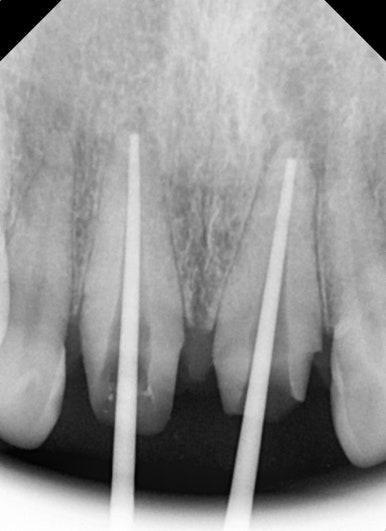

엑스레이 검사 결과, 뿌리 끝에는 염증도 생겨 있었습니다.

단순히 겉모습의 문제만이 아니라, 치아 뿌리 쪽도 치료가 필요했던 상황이었습니다.

25.08.11

25.08.11 기존 크라운 제거 후 모습